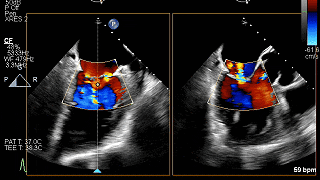

TEE-3D血流

重度DMR,LVEF 61%,LVIDd 5.62cm,LVIDs 3.27cm,VCW 0.72cm,EROA=0.47cm2;RV=83ml,PG mean 3mmHg,PASP 51mmHg。

病变位置为:A1邻近交界处脱垂;宽度/高度:1.08cm/0.29cm;A1/P1瓣叶长度:1.38cm/1.17cm;前后径(AP直径):3.56cm;二尖瓣口面积:4.39cm2